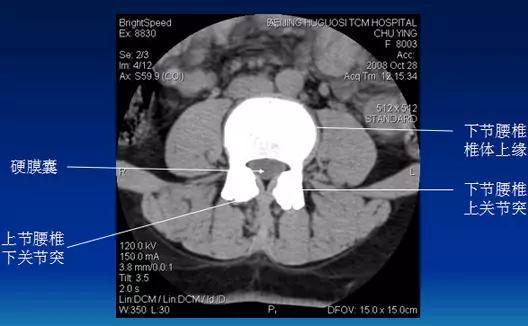

常规腰椎CT扫描层面

常规腰椎CT扫描L3-S1段,分为

(1)椎体层面(骨窗):视察椎体、附件骨质。

(2)椎间盘层面(软组织窗):视察椎间盘、硬膜囊、神经根、韧带等软组织。